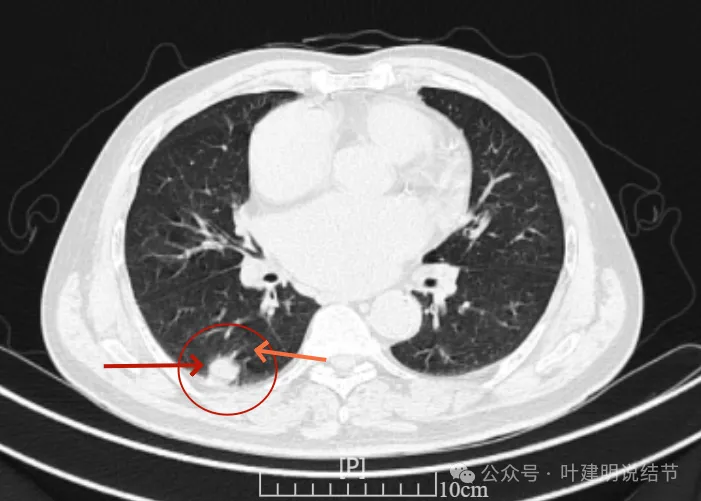

我们先来看2022年3月主要病灶的影像:

右上叶结节实性,密度高,边缘平整,轮廓清楚,像良性些。

右下似见微小结节,实性,与边上小血管截面不太好区分,过小没什么临床意义,能随访。

左下胸膜下实性结节,轮廓稍模糊,密度较高,边缘较光,像淋巴结些,能随访。